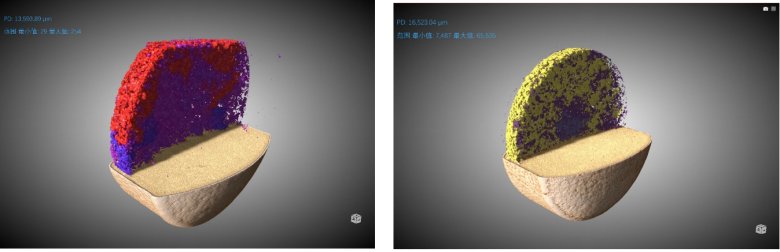

② 推動劑結構形態

左圖為原研藥,右圖為仿制藥。顏色為隨機染色

從上面的圖片、動畫以及數據我們可以得到如下一些信息:

1、 原研藥的整體孔隙率是大于仿制藥的 (2.79% Vs 1.70%)

2、兩款藥的孔隙分布都是隨著孔徑增大而減少的趨勢,但仿制藥的孔徑分布中位數要明顯小于原研藥

3、原研藥的推動劑整體占比也是大于仿制藥的 (5.11% Vs 3.60%)

4、仿制藥的推動劑顆粒均勻度好過于原研藥